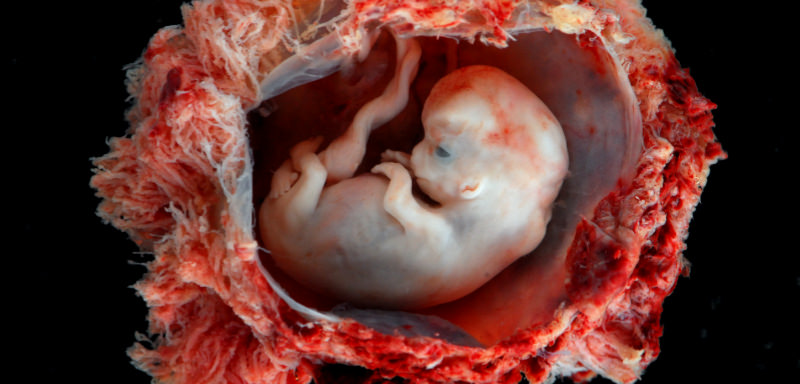

Wenn Abtreibungsbefürworter begründen wollen, wieso Abtreibung gut für Frauen oder wenigstens erlaubt sein sollte, kommt unweigerlich das „Zellklumpen“-Argument…

Mein Kind war ein Kind, Kein „Zellhaufen"

21. September 2020 · Zeugnisse

Als ich das Zimmer im Erdgeschoss betrat, machte der Arzt einen zweiten Ultraschall. Die Krankenschwester verweilte eine endlose Minute lang mit starrem Blick a…